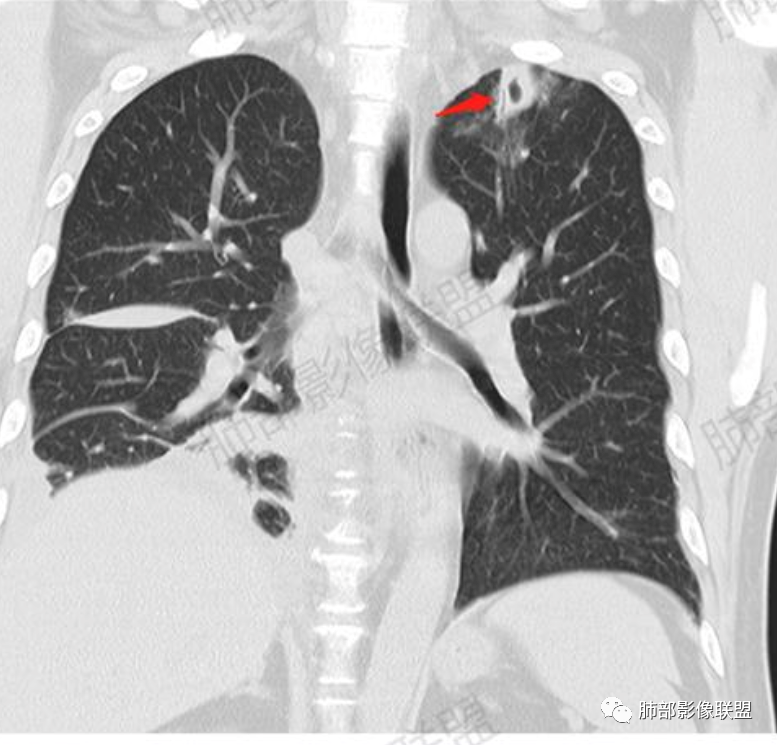

尘缘: @赵永兵 内蒙巴市临河妇幼影像科 左上肺也是胸膜下(胸膜顶下)的SPE。

这个图就是理由

尘缘:

@赵永兵 内蒙巴市临河妇幼影像科 支气管是从旁边经过,所以不是空洞,是胸膜下的脓毒栓。如果是结核空洞,应该与支气管相通(因为结核没有血播感染表现的时候,来源是气道,空洞应该与支气管相通),所以支气管从旁边经过,这病灶又在胸膜下,周围也没有干酪坏死。当然是SPE了。